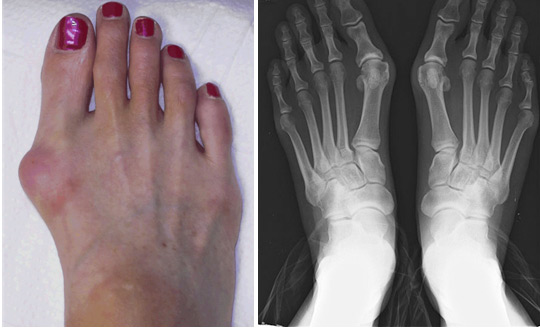

Čukljevi